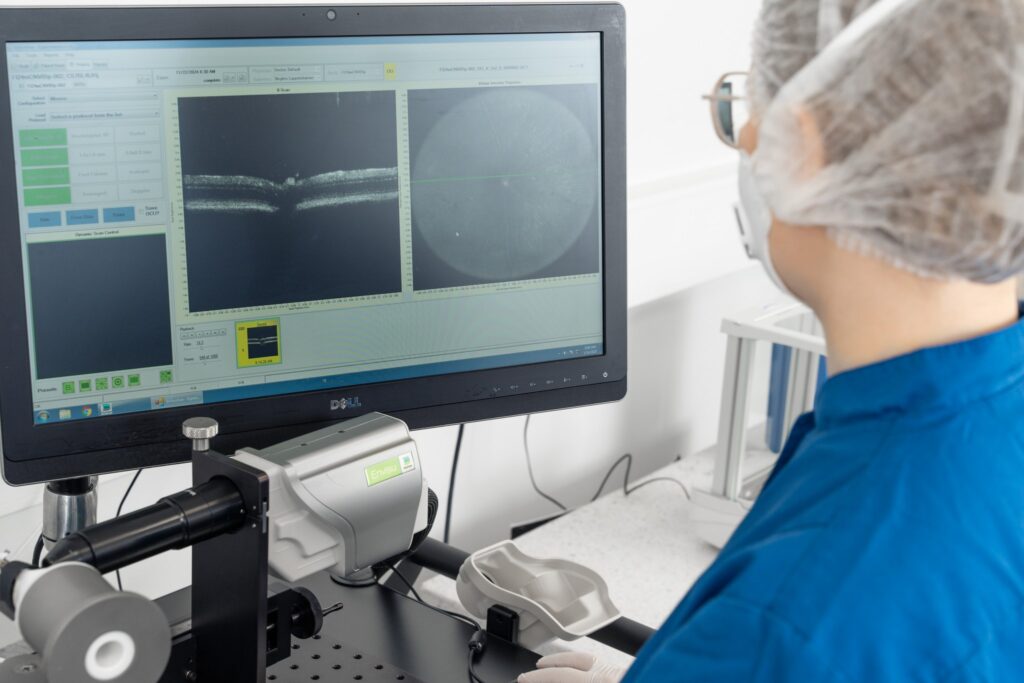

Clinical evaluation of uveitis severity is performed by an experienced veterinarian using slit-lamp biomicroscopy and scored according to the Modified Hackett-McDonald and the SPOTS (Semiquantitative Preclinical Ocular Toxicology Scoring) grading system.

Clinical scoring (Slit-lamp ophthalmic examination)